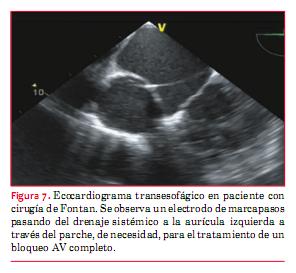

Bradiarritmias

El tratamiento de las bradiarritmias sintomáticas en pacientes con CC es la estimulación cardíaca. Igual que para los DAI, dada la distorsión anatómica habitual luego de una cirugía, se debe analizar con detalle la vía y los sitios de implante de los dispositivos. Los pacientes con corazón univentricular posanastomosis cavopulmonar total carecen de acceso venoso al corazón, por lo cual se deben considerar distintas alternativas para el implante del marcapasos(19). Si se tiene la necesidad de dejar un electrodo por vía sistémica debemos saber que tiene riesgo de accidentes tromboembólicos y requerirá siempre anticoagulación crónica (figura 7). Por tal motivo, la vía epicárdica es la más utilizada aunque el resultado y la duración a largo plazo de los electrodos es inferior a los endocavitarios.

Dado que el implante de un sistema epicárdico requiere de esternotomía, en muchos centros, cuando deben abordar el mediastino, ya dejan electrodos conectados y abocados a un fácil acceso por si se necesitan en el futuro. Como alternativa a la vía epicárdica puede utilizarse la vía transatrial, colocando catéteres endocavitarios a través de la pared de la aurícula. Las indicaciones precisas de implante exceden a esta revisión y se remite al lector a las guías respectivas(33).